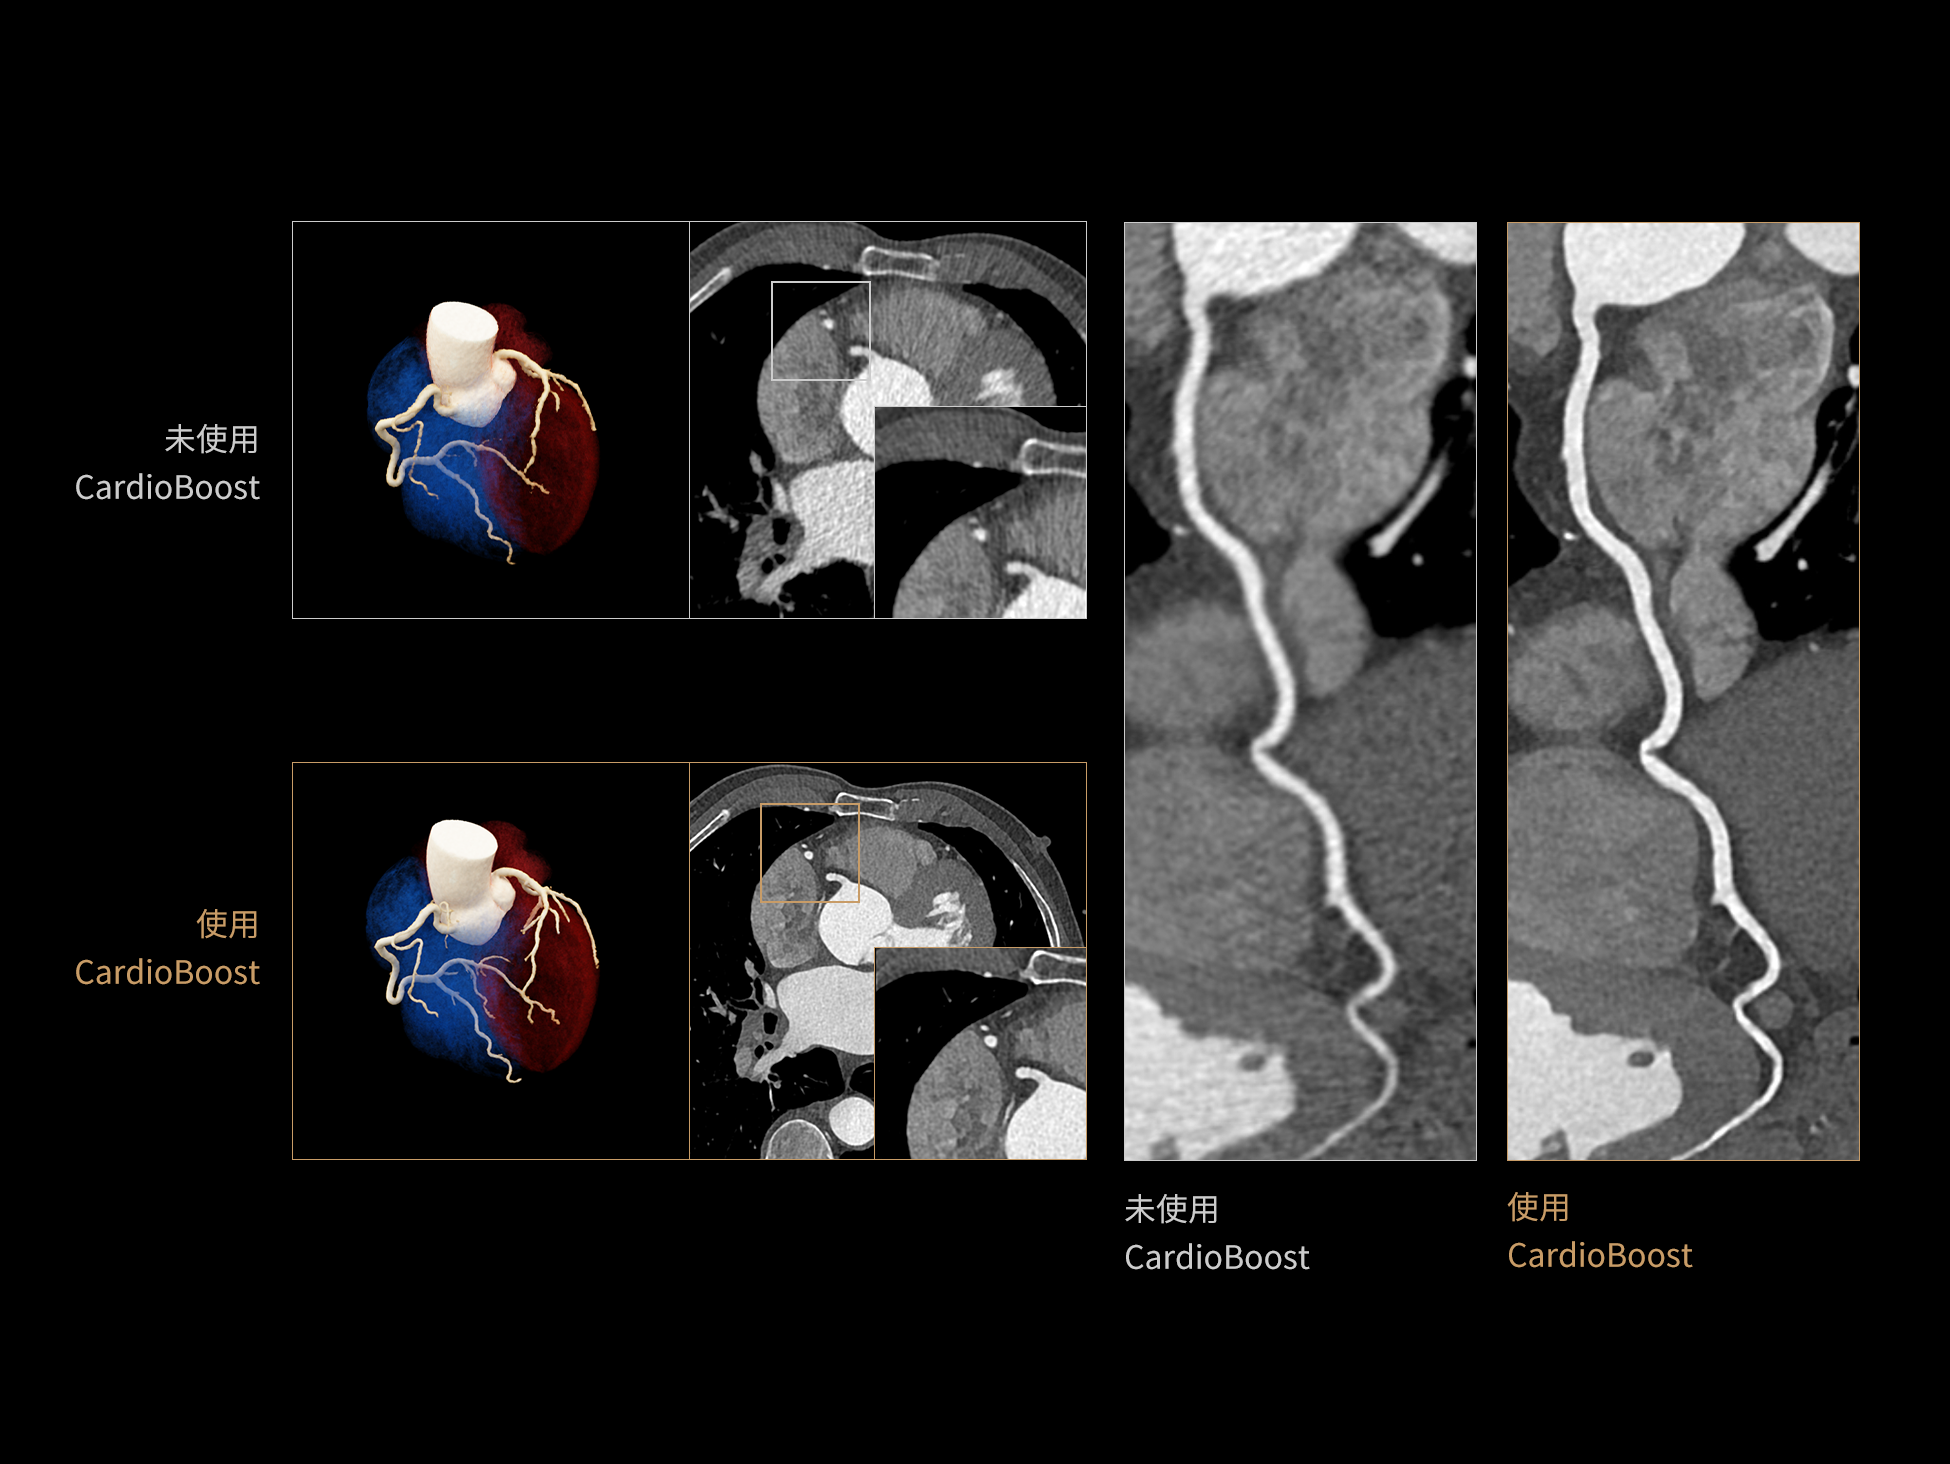

CardioBoost:专属网络设计,重塑心脏影像表现

目前心脏的 CT 检查还存在辐射剂量偏高、空间分辨率不足、 致密钙化伪影影响冠脉狭窄程度评估等方面的限 制[1][2]。CardioBoost 技术专为心脏 CT 高清成像而开发,通过 3D 神经网络的深度学习技术,利用先进的注意力机制在识别关键成像特征方面的出色表现,能够精确地聚焦于斑块、支架以及微小血管等关键细节,清晰展示这些结构与冠脉血管的边界,从而显著提高诊断的准确性,并提升医生的诊断信心。创新的 CardioBoost 心脏图像重建算法,不仅实现了图像清晰度的提升和伪影的去除,更能在减少辐射剂量的同时,保证心脏图像的高质量和图像纹理的自然。

CardioBoost核心创新

采用 3D 神经网络的空间结构优势与精细的组织分类能力,CardioBoost 技术优化了组织对比,高清展示血管斑块,使斑块与血管边缘的轮廓清晰可辨,提升斑块诊断与评估的精确性。

借助 3D 神经网络设计、空间注意力机制聚焦与特征强化作用,CardioBoost技术提升图像的空间分辨率,实现冠脉支架的高清成像,对支架形态与管腔通畅度的评估更精准。

CardioBoost 整合先进的 3D 神经网络和空间注意力机制,大幅增强数据处理的速度与精确度。该技术能有效抑制由致密钙化引起的晕状伪影,清晰展现钙化斑块的原始结构和大小,对冠脉狭窄的评估更加精确可靠。

对比度强化模块

分辨率强化模块

伪影抑制模块